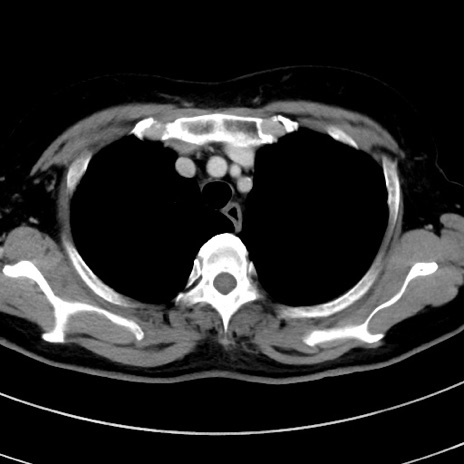

症例9(横断像)

【症例】 60歳代女性

【主訴】むかつき、みぞおちの痛み

【現病歴】3日前よりむかつきがあり、食事がとれない。

【既往歴】糖尿病

【身体所見】発熱なし、心窩部圧痛軽度あるも、腹膜刺激症状なし。

【データ】WBC 7400、CRP 1.92